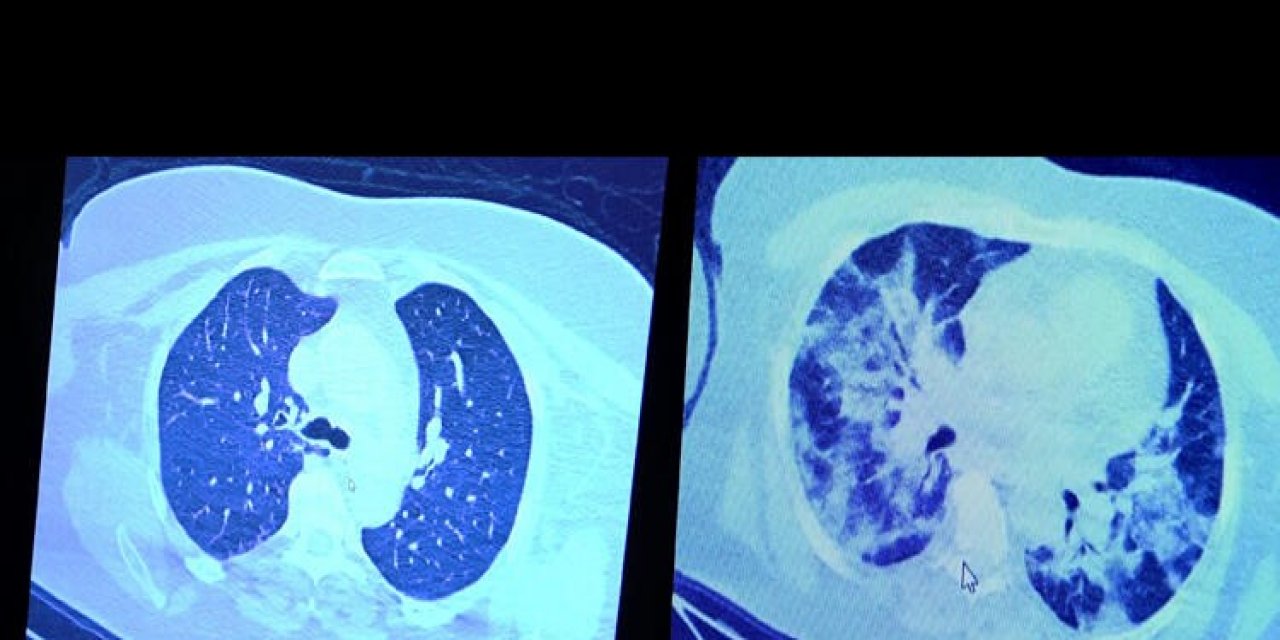

Koronavirüs hastalarının bakanlık tarafından verilen koronavirüs ilaçlarını kullanmaktaki tereddütleri devam ederken, Prof. Dr. Şevket Özkaya, ilaç kullanan ve kullanmayan koronavirüslü hastaların akciğer tomografisini inceledi. Koronavirüs teşhisi yeni konan hastasının tomografisini inceleyen Özkaya, akciğer tomografisinde tutulumun az olduğunu gözlemledi. Verilen ilaçları kullanmayan hastanın 1 hafta sonraki tomografisinde ise akciğerin sıvı ile dolduğu tespit edildi.

Prof. Dr. Şevket Özkaya, "Ekranda 55 yaşında bir kadın hastamızın filmini görüyorsunuz. Bu kadın hastamız acil servisimize ateş şikâyetiyle geldi ve koronavirüsünden şüphe ettik. Testini yaptığımızda ise testin sonucu pozitif geldi. Tomografi çektiğimiz zaman akciğerlerinde henüz ciddi bir tutulum görünmezken hastamız 55 yaşında olduğu için her an ilerleyebilir korkusuyla Sağlık Bakanlığımızın önerdiği ilaçları ve reçeteyi hastanemizden kendisine verdik. Hasta kendini evde karantinaya aldı fakat sonradan öğrendik ki tereddüt ettiği için ilaçlarını kullanmayarak kendini evde tedavisiz bırakmış. Yaklaşık bir hafta sonra aynı hasta acil servisimize bu sefer solunum yetmezliği şikâyetiyle geldi. Solunum yetmezliği gelişince hastanın akciğer tomografisinde ‘buzlu cam’ dediğimiz ve daha ileri konsolide alanların oluştuğunu gördük. Yaygın akciğer harabiyeti dediğimiz bir tablo oluşmuştu. Bu durumda hastada solunum yetmezliği olduğu için yoğun bakıma almak zorunda kaldık" diye konuştu.